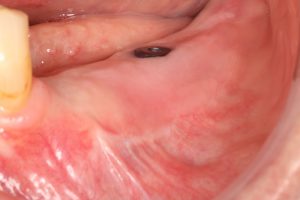

When accessing the area that has to be reconstructed through a subperiosteal tunnel, and performing the whole procedure through the tunnel approach will give us two significant advantages:

1. No incisions are made over the crest, so no suture will be there, reducing to zero the possibility of wound dehiscence

2. As far as no incisions are made over the periosteum that is covering the graft, its osteogenic and revascularization capacity remains intact.

Using a different approach to crestal incision like tunnel approach.

#1. The Tunnel Approach Technique